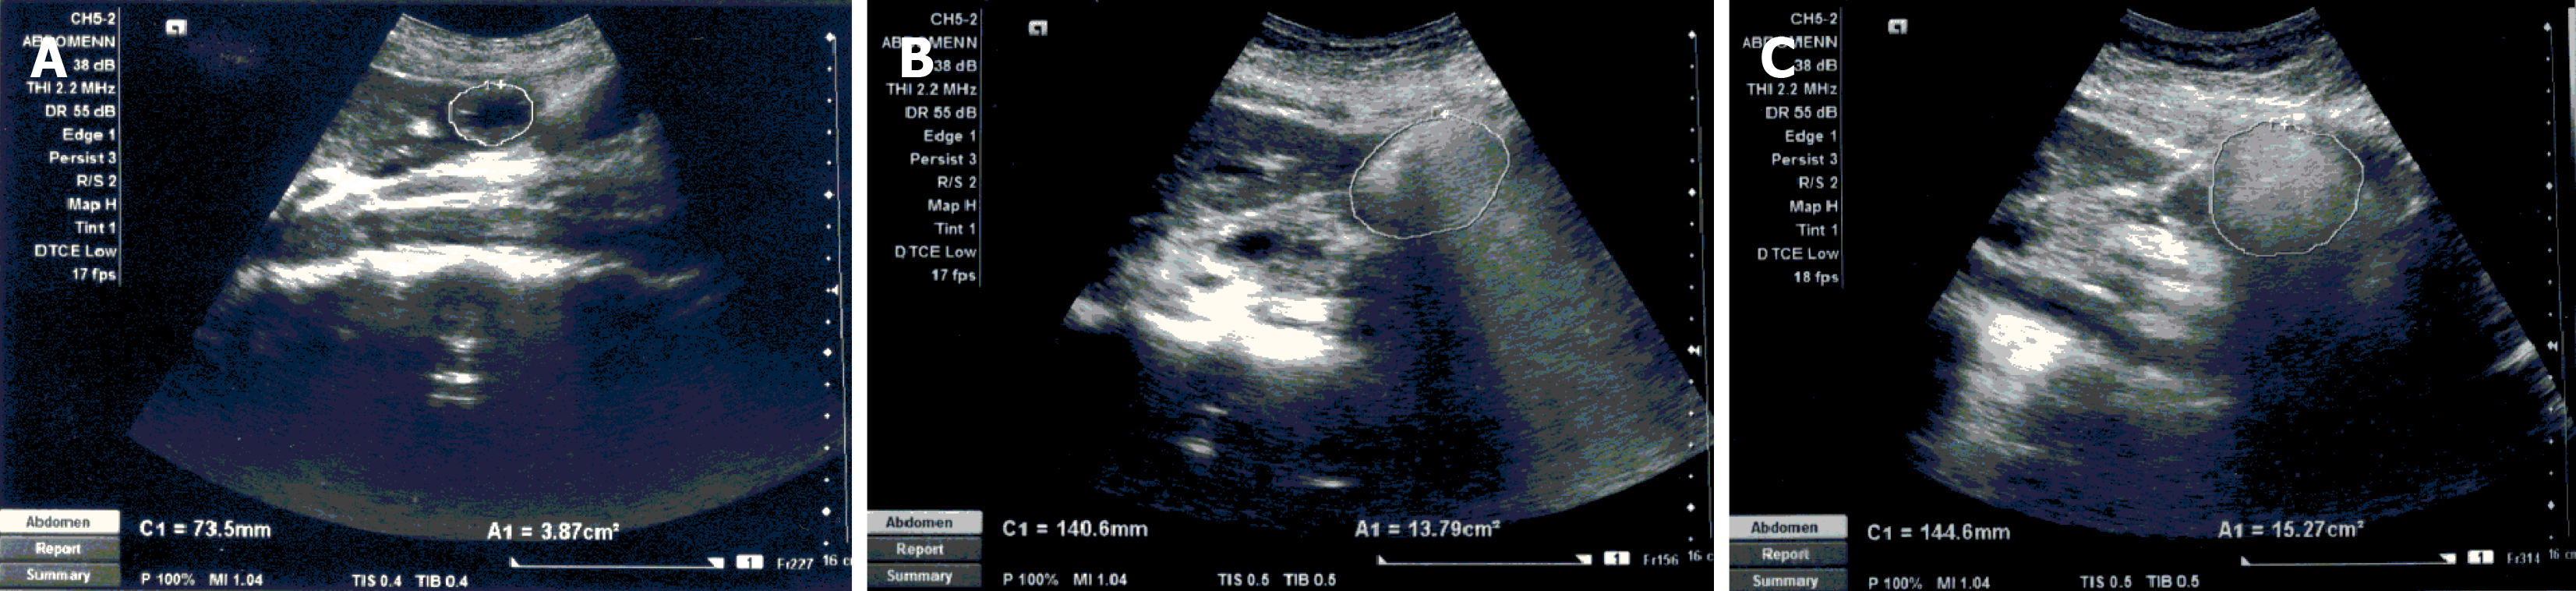

The gastric motility assessments were performed in the morning after an overnight fast of 8 hours. The subjects were examined by real-time ultrasonography performed with a high-resolution real-time scanner (SIEMENS ACUSON X300, Thailand) with a 3.5 MHz convex array transducer with facilities to record and playback. Gastric motility assessments in all patients commenced between 8:00 am and 8:30 am. Both gastric motility measurements of each patient were made by the same examiner, who was blinded with respect to the test meal. The subjects were examined in a semi-recumbent position and rested in a seated position in between measurements. The antrum, superior mesenteric artery and abdominal aorta were simultaneously visualized by the transducer (Figure 1). The record-and-playback technique was employed to enhance measurement accuracy.

Figure 2A shows the median residual gastric antral areas after ingesting solid and semisolid meals. Gastric residual antral area following both meals showed a similar biphasic pattern for the first 3 hours after the meal, with a lag phase of 60 minutes. The half-emptying time was approximately 120 minutes for both meals. The median GER of both meals did not differ significantly up to 3 hours post-ingestion, after which the solid meal emptying was slower (Figure 2B). At the end of 4 hours, the mean percentage emptying of the semisolid meal was 81.1%, and of the solid meal, it was 70.6%. In the semisolid meal, GER at 90 minutes significantly correlated with the GER at 240 minutes (r = 0.594, P = 0.042). There was no such correlation in the solid meal between 90-minute and 240-minute GERs (r = 0.055, P = 0.852). The median GRR (Table 1) and antral motility index (Figure 2C) at each time point did not differ significantly between the two meals. GER of the two meals showed a significant positive correlation up to three hours of post-ingestion (Table 2).